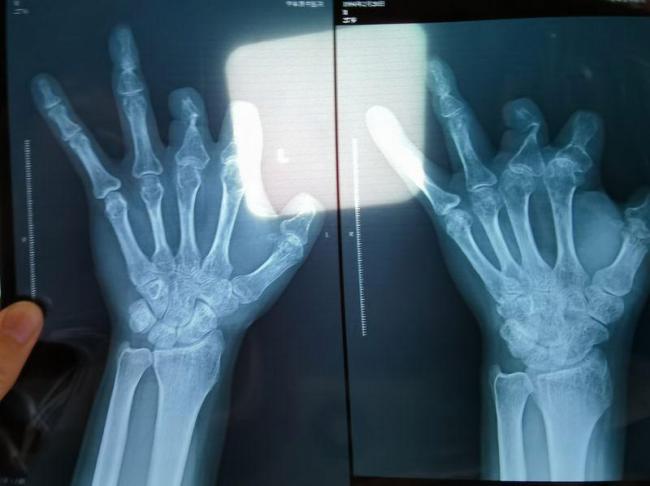

单价1.68万的器材植入体内后消失 手术器械疑云。单价1.68万元的微血管吻合装置在王海森的X光片上消失了。这种装置带有不锈钢针,不可能被人体吸收,唯一的可能就是手术时没有使用。尽管之前有人向他透露过这一点,但直到看到片子前,王海森一直都不相信。

2017年11月29日,医药代表何某帝接到王福建助理的电话,让他多送些微血管吻合装置到医院。当天进行的是彭先生的“断指再植”手术。彭先生提供的医疗费用清单显示,手术当日他使用的医用材料费共计14.3万元,仅微血管吻合装置就占了10.08万元。该装置单价1.68万元,术中使用了6个。术后彭先生委托律师欲将郑大一附院诉至法庭,并在律师指导下拍摄了X光片,发现术中使用的6个吻合装置都“消失”了。

该产品的代理商证实,微血管吻合装置为植入型医疗器材,患者拍摄X光片时会有显示。彭先生和王海森的情况并非个例。2018年,王海森被电锯伤到左手,导致拇指关节以上部位被切掉,工友将其送入郑大一附院急诊科。手术次日,王海森因觉得费用太高办理了出院手续。一年后,有人告诉他这个价格昂贵的进口器材并没有在手术中使用。直到2025年12月,王海森在老家拍摄了左手X光片,确认手术部位的确没有微血管吻合装置。